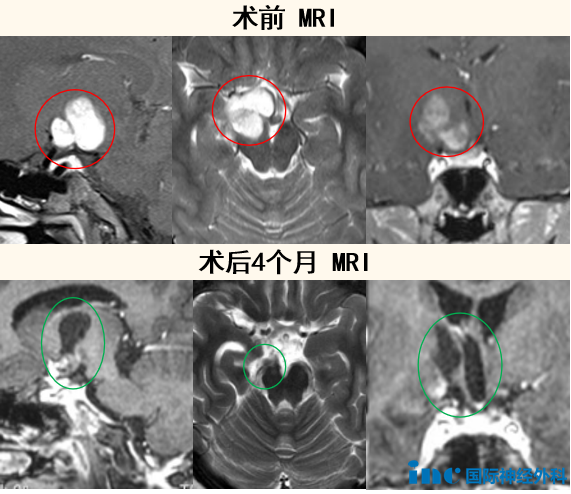

7岁男孩,脑干几乎被肿瘤压没,术后4个月成为运动小健将

一个几乎将脑干压“没”了的巨大恶性肿瘤(弥漫性中线胶质瘤,H3K27M突变,WHO 4级),让7岁的小勇状态急剧恶化,“已经走不了路,只能坐轮椅。长了有0.9公分,一天的时间(病情进展)已经很快了。”父母跨越几百公里,从诊断到决定找巴教授手术,他们仅用了48小时,成功换回小勇的生命。在巴教授成功手术后,小勇当天就能开口说话,第二天动作如常,两周后顺利出院。点击阅读:一天激长9mm!被高级别胶质瘤困在轮椅上的他,仅4个月后成为运动小健将!